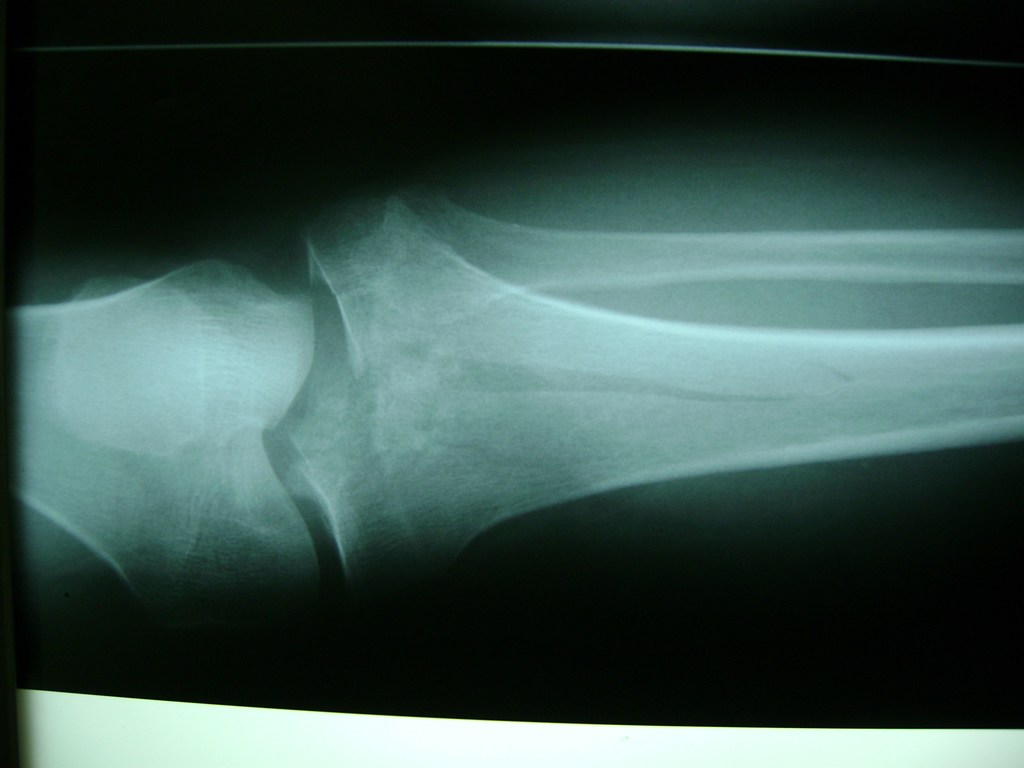

La artroscopia de rodilla es un cirugía en el cual la estructura interna de la articulación es examinada ya sea para realizar un diagnostico o para realizar un tratamiento, este procedimiento se realiza utilizando un instrumento parecido a un pequeño tubo llamado artroscopio.